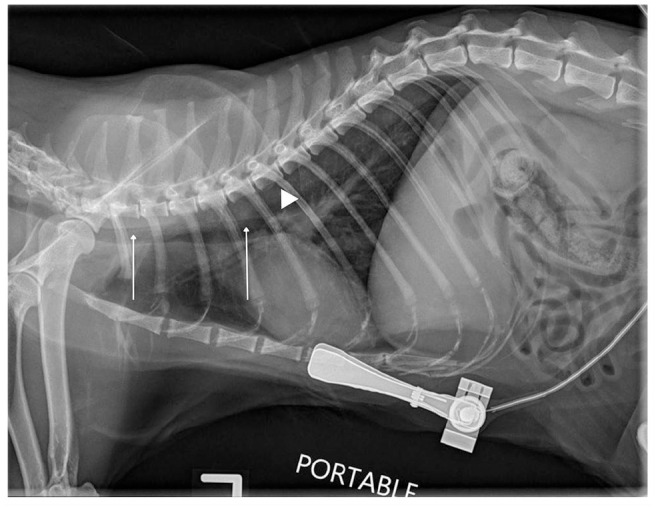

Case series summary: Two cats were referred to a veterinary teaching hospital with a cotton tip applicator (CTA) tracheobronchial foreign body (FB) after induction of anesthesia for an elective dental cleaning. In both cases, a lidocaine-saturated CTA, utilized to desensitize the larynx before endotracheal (ET) intubation, broke when introduced into the oropharynx and was subsequently aspirated into the tracheobronchial tree. Both CTAs were successfully removed bronchoscopically, and the cats survived with no short- or long-term complications noted.

Relevance and novel information: Utilizing a lidocaine-saturated CTA to facilitate ET intubation in cats is not well described, and information on the relative risks and benefits of this specific method for laryngeal desensitization is lacking. This retrospective case series is the first to describe a complication of this technique and successful treatment. These cases highlight the risk inherent to using a CTA to desensitize the feline larynx.